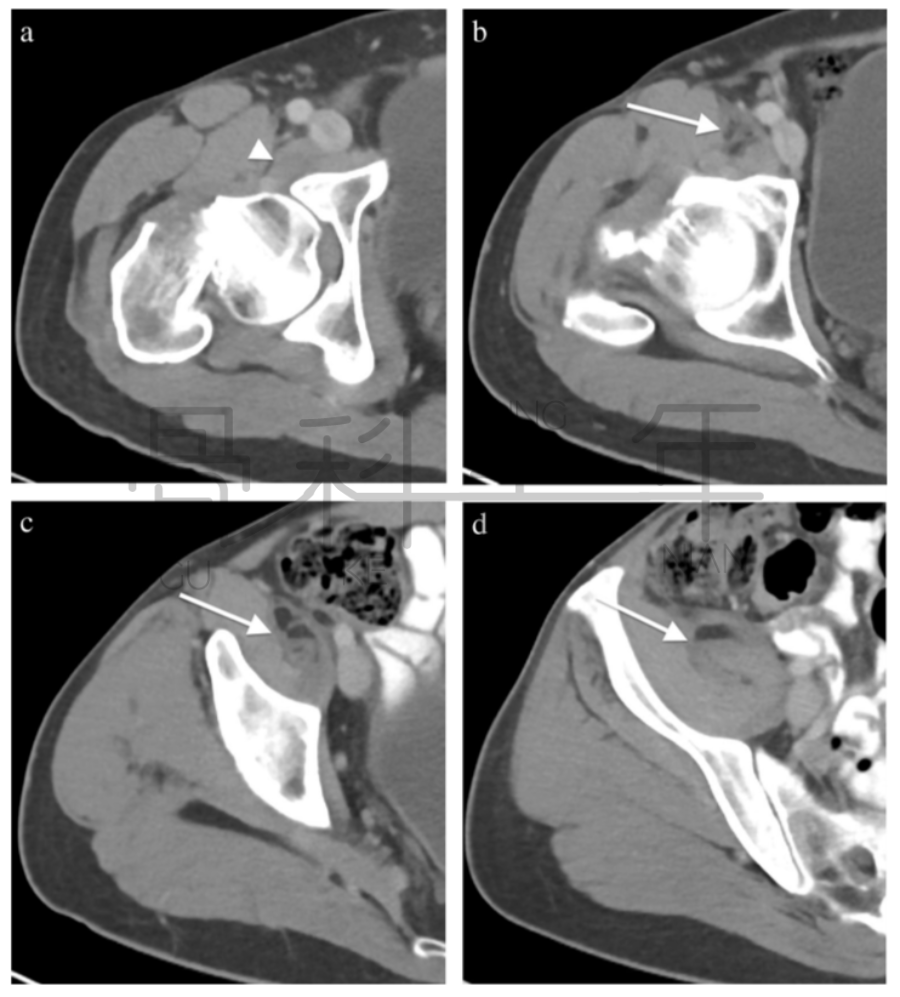

病例4股骨颈骨折,在CT横断面骨窗上未见明显液体分层(a),在软组织窗(b)可见高密度血肿影(箭头所示,CT值为50HU)。

病例5股骨颈骨折,在CT横断面软组织窗上可见在髂腰肌内出现积脂血症表现。

病例6 一例82岁髋部外伤患者,非移位股骨颈骨折,在CT横断面可见积脂血症,MR证实股骨颈骨折。关节积脂血症在非移位股骨颈骨折的识别中作用明显。